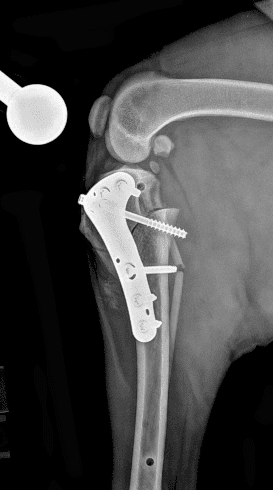

정형외과 전공의 수의사가 직접 수술합니다.

02C-arm을 통해서 좀 더 섬세한 정형외과 수술을 진행하고, 본원에서는 외과적 침습을 최소화 하는 중재적 시술 (기관 협착, 동맥관개존증(PDA), SUB 등)을 진행하고 있습니다.

12정교한 정형외과 도구를 사용하여 신속 정확한 정형외과 수술이 가능

13수술 중 골절 상태 혹은 이식물 적용 후 상태 등 육안으로 명확히 확인하기 힘든 상태를 X-ray 확인하여 정확한 수술 결과를 만들어 내는 것이 가능